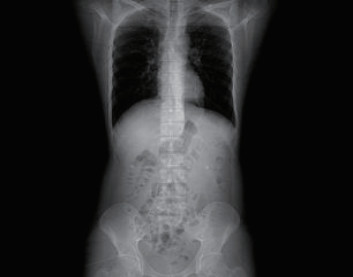

1 一般资料患者,男性,32岁,职员,因“误吞金属钉状物7 d”就诊。患者7 d前误吞入金属钉状物一根(大小约3 cm),患者无明显不适症状,未诊治。4 d前出现下腹隐痛,行急诊全腹CT检查,见图 1,行急诊胃镜检查未见明显异物。后复查腹部CT示异物进入小肠内(图 2),普外科会诊建议随访。2 d前复查腹部CT(图 3),继续保守治疗。1 d前患者为行异物取出入院,复查腹部CT可见异物至结肠内(图 4)。急诊予以聚乙二醇电解质散导泻清肠,行无痛肠镜下异物取出术。本文已通过本院伦理委员会审批,伦理审批号为:(2021)伦审研第(0252)号,并通过免除知情同意申请。完善术前检查,进行药物导泻清肠时,关注患者有无腹痛等现象,以免因服用药物清肠,肠蠕动加快,尖锐异物在消化道内随蠕动前行,尖端嵌插在肠壁中而停滞不前,并随着后方内容物的推进,加深尖锐异物刺入肠壁,最终导致穿孔及出血的发生。本例患者安置在独立单人间进行肠道准备,不定时进行腹部查体及观察排泄物的性状,早期发现穿孔、出血指征,以便尽早进行外科手术干预。与此同时,内镜中心医护人员联合外科、放射科、麻醉科医生制定诊疗方案,若发生此类情况,立即予急诊行腹部X线或CT检查,一旦确定出现穿孔或出血等情况,即刻行急诊手术治疗。

| 图 4 腹部CT示回盲部致密影,提示异物 |